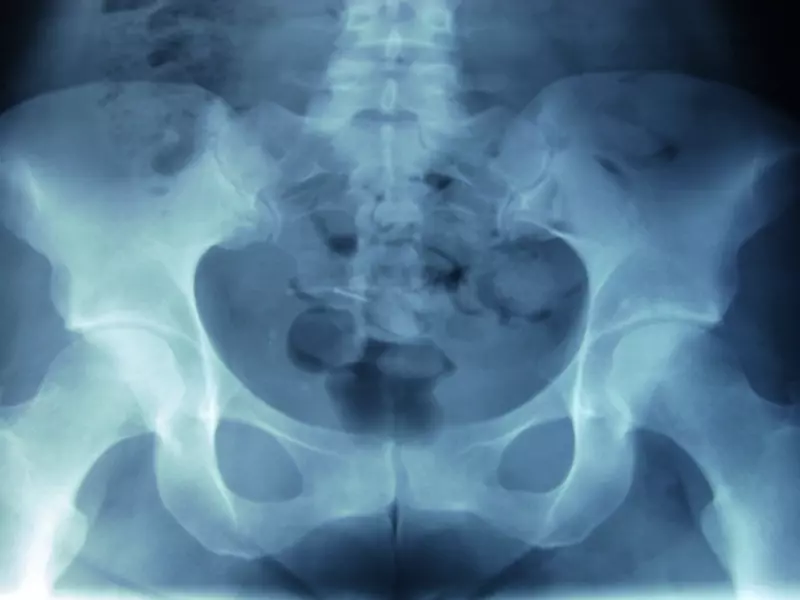

Staw kolanowy jest najbardziej złożonym i największym stawem w ciele człowieka, jak również jest jednym ze stawów, które są najbardziej narażone na uszkodzenia.

Na staw kolanowy składają się takie elementy jak:

• dalszy odcinek kości udowej, utworzony przez dwa zaokrąglone kłykcie (przyśrodkowy oraz boczny), które są ustawione w stosunku do siebie rozbieżnie. W przedniej części pomiędzy kłykciami znajduje się powierzchnia

• rzepkowa;

• koniec bliższy kości piszczelowej, utworzony przez dwie powierzchnie kłykcia przyśrodkowego oraz bocznego. Powierzchnie przedzielone są wyniosłością międzykłykciową z dwoma guzkami (przyśrodkowym i bocznym) oraz są miejscem przyczepu więzadeł krzyżowych oraz łąkotek. Na przedniej powierzchni stawu kolanowego znajduje się rzepka.

Rzepka to spłaszczona kość znajdująca się na przedniej powierzchni stawu kolanowego. Powierzchnie stawowe są pokryte warstwą chrząstki szklistej będącej wyspecjalizowaną tkanką łączną. Chrząstka stawowa nie zawiera naczyń krwionośnych oraz limfatycznych, dlatego jej odżywianie pochodzi głównie z płynu maziowego.